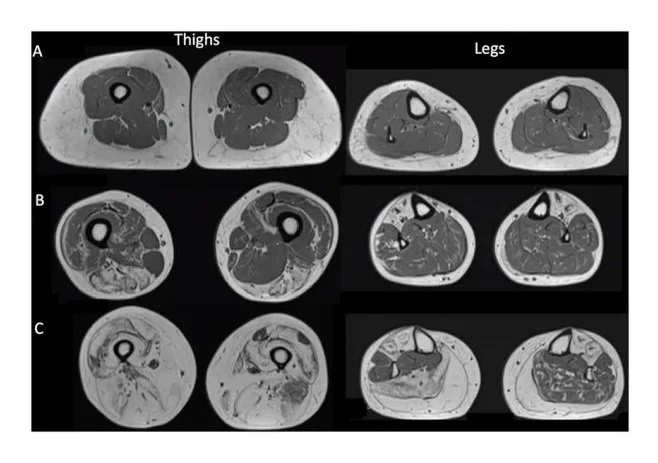

10. Muscle Inflammation & Sarcopenia/Muscle Atrophy: How Much Do You Have? Unless You Get Scanned You Don't Know

This image on the left shows a series of MRI scans through the legs and thighs of elderly people with various stages of sarcopenia or muscle wasting which increasingly afflicts most people from the age of 50 when fatty infiltrates gradually replaces their healthy muscle with inflammatory fat. Sadly, over the years they were allowed to accumulate visceral fat never identified, much less eliminated. The consequences can be seen here. Wouldn't you like to know if this was happening to you .... yet it is not even commented on by physicians because they are neither trained to identify it nor do anything to correct it. Reversing sarcopenia and chronic disease is one of my passions. If you ever had an MRI or CT, ask to get the images and look at them yourself because unless the system can make money on it you won't ever hear about it or do anything to correct it.